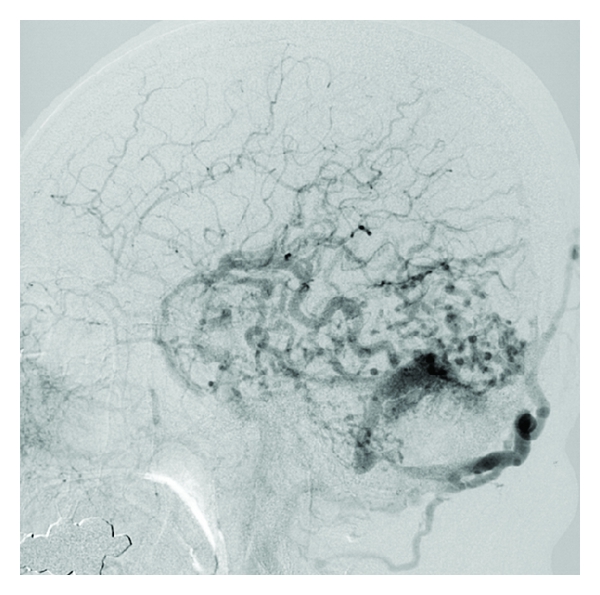

Part of this case has already been reported previously [2–4]. A 46-year-old male had been treated with antidepressants to depression at a local hospital for four years. The patient was temporarily laid off due to his depression. Afterwards, he became poor at ordinary conversation with his wife. Therefore, she took him to the local hospital. Because a cerebrovascular disease was suspected in the institute and the patient was recommended to consult neurosurgery, he came to our hospital on the same day as onset of the symptoms. On admission, the patient exhibited acalculia, finger agnosia, right-left disorientation, agraphia, and hemispatial agnosia. A CT scan was obtained immediately. Multiple high density spots were evident in a wide area of the left temporal, parietal, and occipital lobes on plain CT scan. They were thought to be dilated draining cortical veins. The left transverse-sigmoid sinus corresponding to the draining sinus also became larger than the right side on the CT scan [2]. A cerebral angiography was subsequently performed. A DAVF in the left transverse-sigmoid sinus with cortical vein reflux in the left temporal, parietal, and occipital lobes was demonstrated on the left common carotid artery angiogram. Its feeding arteries were the left occipital artery, posterior auricular artery, middle meningeal artery, and superficial temporal artery (Figure 1). After the examinations, the patient was admitted to the intensive care unit. In a former axial image of 3D-CT angiography arterial phase obtained after admission, abnormal vessels appeared in the left cerebral hemisphere including the left dorsolateral prefrontal cortex (DLPFC) (Figure 2). After the three endovascular surgeries [4], the DAVF including the cortical vein reflux disappeared on the angiogram (Figure 3). The patient did not experience any complications during and after these procedures, and his depression as well as Gerstmann’s syndrome was improved. The quantity of the antidepressants for the patient decreased after the treatment, and the patient returned to work without any antidepressant two years after the treatment.